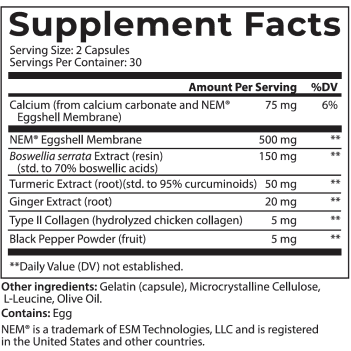

And to be 100% transparent, I’d like to show you the label that appears on every jar we ship.

Joint Support is an excellent addition to your daily routine…

And it’s so easy to use.

Simply take two capsules daily and that’s it.

In just a couple of seconds, you’ll take a huge step towards better joint health.

Personally, I recommend you take it first thing in the morning, like a daily multivitamin so you always remember to take it.